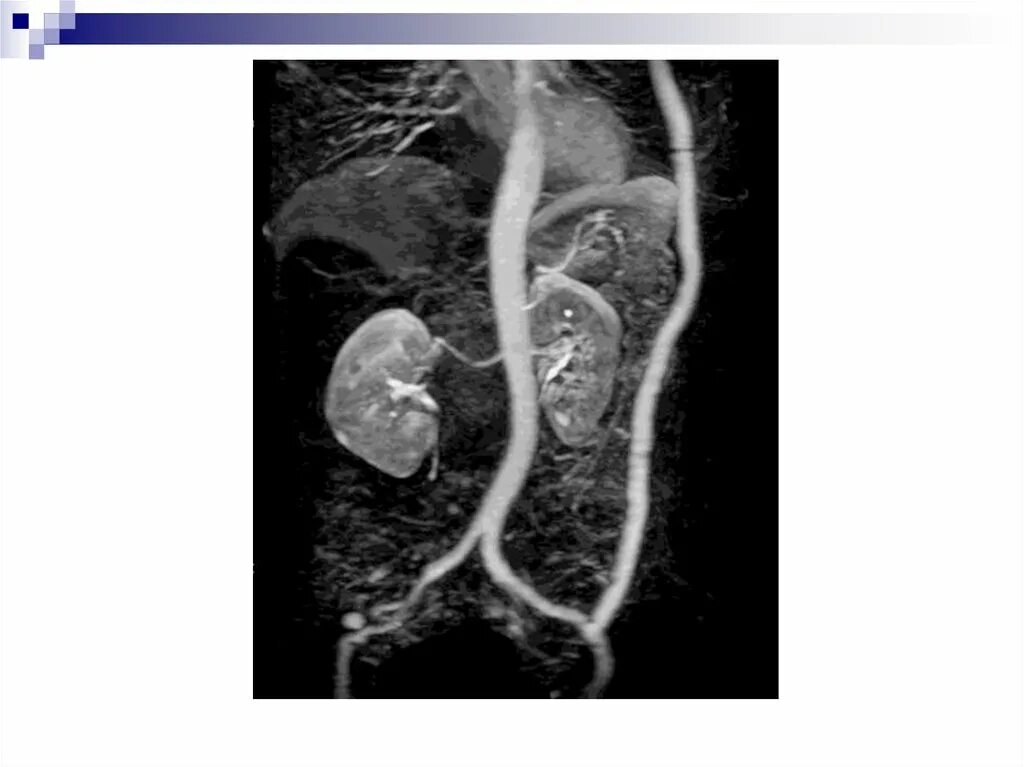

Кальциноз брюшного отдела